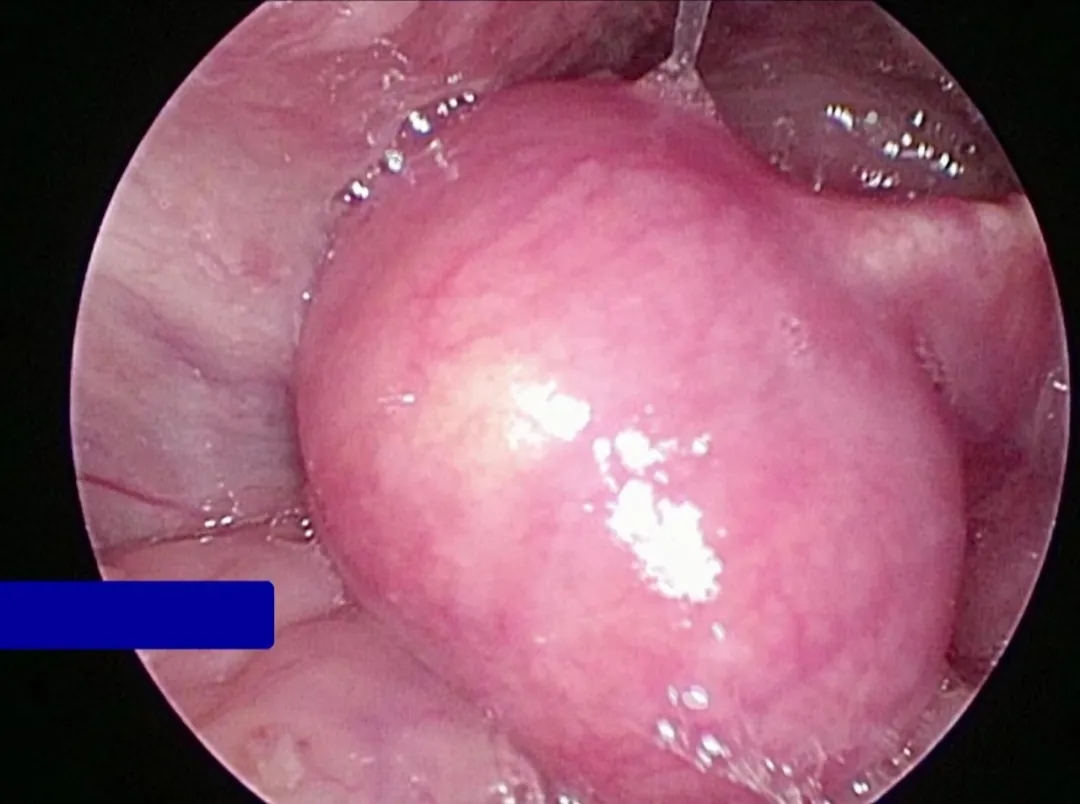

我進(jìn)行了電子喉鏡檢查

困擾我已久的謎團(tuán)終于被揭開

——會(huì)厭囊腫

這個(gè)小小的囊腫

大約有花生米大小

卻占據(jù)了我喉嚨的深處

悄然侵蝕著我的健康